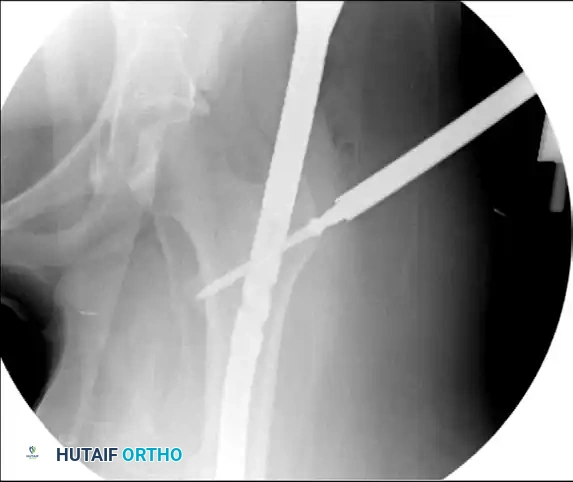

Figure 55-63B: Intraoperative fluoroscopic view after placement of an antegrade intramedullary nail. Note the appearance of the proximal femur.

Figure 55-63C: Intraoperative fluoroscopic view after range of motion of the hip under live fluoroscopy reveals the previously occult femoral neck fracture.

Figure 55-63D: Intraoperative fluoroscopic view after removal of the standard proximal interlocking screw, adjustment of the nail, and successful placement of reconstruction screws.